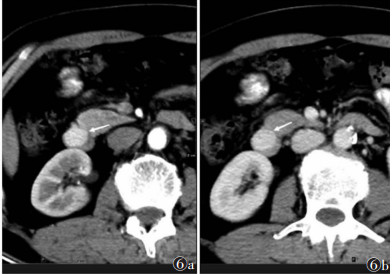

| 图 6 男,61 岁,十二指肠降段小 GISTs,腔内型(白箭) 图 6a CT 增强扫描动脉期病灶 CT 值 132 HU 图 6b 门静脉期 CT 值 130 HU |

2 结果 2.1 一般资料56例中,位于胃49例,其中贲门区12例(图 1)、胃底21例(图 2,3)、胃体15例(图 4,5)、胃窦1例,小肠4例(图 6),结直肠1例(图 8),肛周1例(图 7),胃肠道外1例。传统开腹手术6例,腹腔镜手术9例,内镜下黏膜剥离术(ESD)26例,内镜下全层切除术(EFR)15例。56例核分裂象均≤5/50 HPF,CD34、DOG-1均呈阳性;SMA阳性4例,阴性52例。肿瘤危险度(NIH改良版):极低危55例,高危1例(瘤体破裂出血,图 8)。